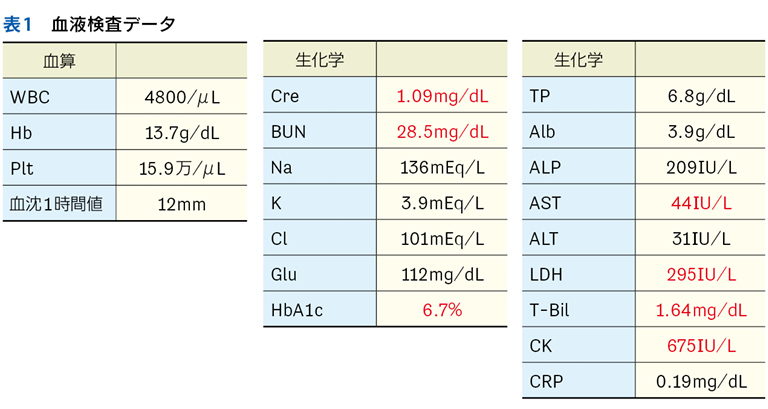

Case 1

独居の高齢者が自宅内で倒れている状態で発見され搬送された。最終健常は5日前。頻脈,SpO2低下,意識障害,感染徴候を伴う褥瘡,急性腎障害,高ナトリウム血症,クレアチンキナーゼ高値,炎症反応亢進,膿尿がみられている。

▶ この患者は何らかのイベントを契機に動けなくなり,長時間倒れていたものと推測される。多数ある「プロブレム」の中には,最初のイベントに直接起因するものもあるかもしれないが,大部分は倒れていた結果として生じてきたもの(最初のイベントの診断という観点では「ノイズ」)だろう。こういった患者が「脱水症」とか「横紋筋融解症」としてのみ治療されているケースをよく見かけるが,これは表層に現れた二次的,三次的な現象を取り上げているだけであり,最初のイベントの鑑別と治療が本来必要である。